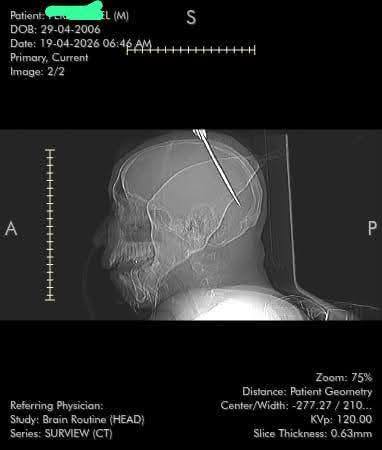

Doctors at the Georgetown Public Hospital Corporation have successfully saved the life of a 19-year-old Cuban national who arrived with a knife embedded in his skull after an altercation.

Emergency teams quickly stabilised him before scans confirmed the blade had penetrated his brain and caused internal bleeding.

Specialists performed emergency surgery around 4 a.m., carefully removing the object.